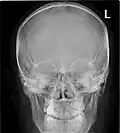

CT scans, radiographs (X-rays) and other illustrations

Paranasal sinuses radiograph (occipitomental) -